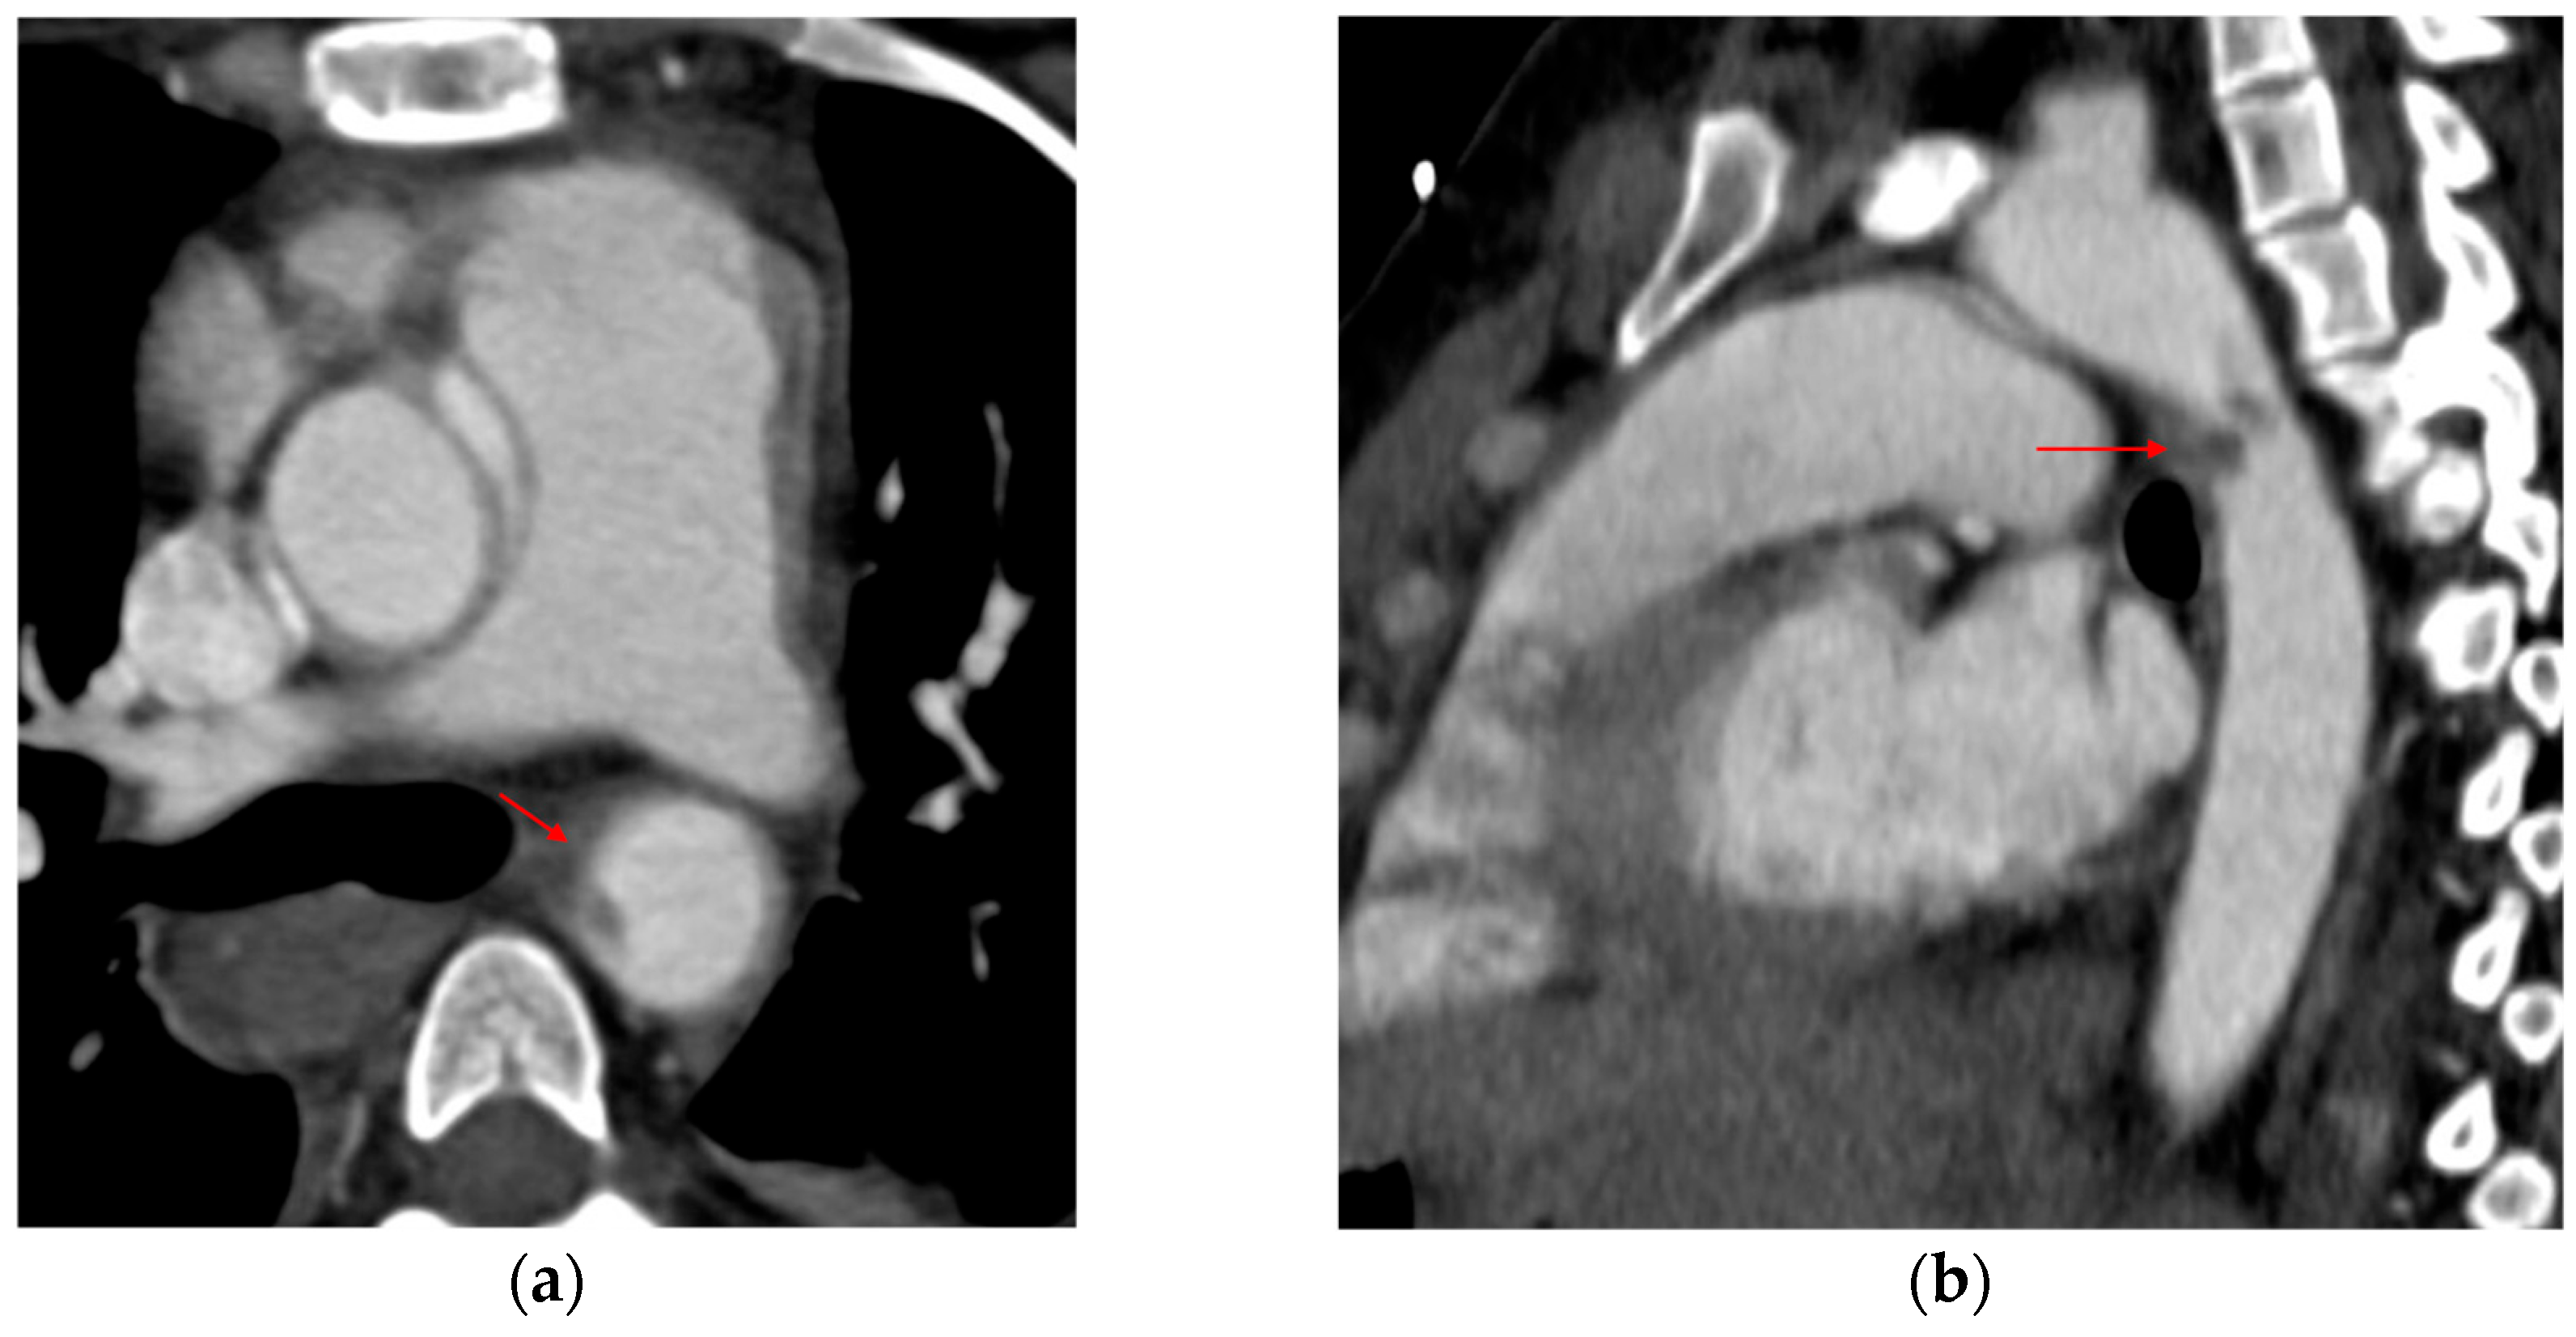

3.1.3. Mimics and Anatomic Variations

3.1.5. CT Angiography Artifacts

3.1.6. ECG-Gated CT Angiography